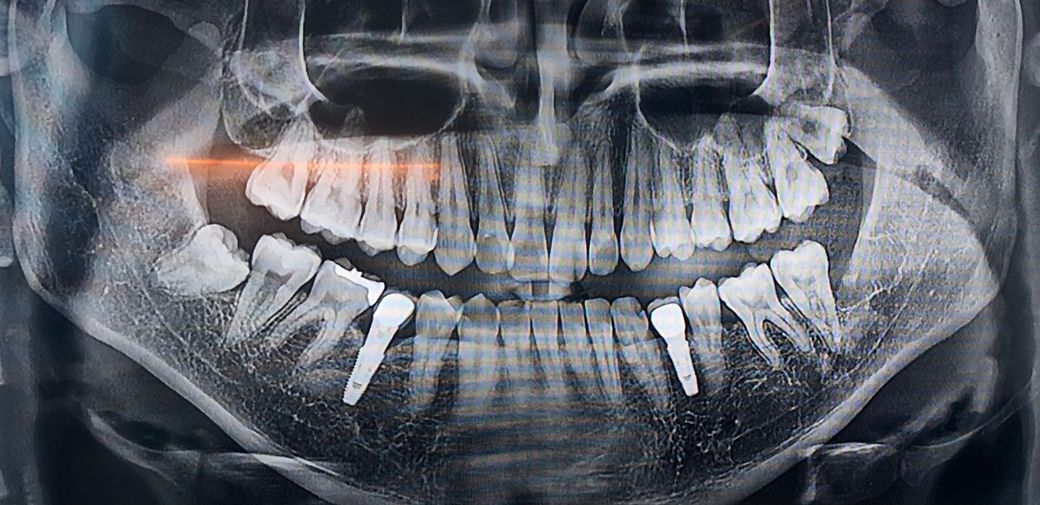

사랑니 발치를 해야 하는데 사진을 보고 난이도 가 어려운지 쉬운지 대략적으로라도 알려주세요

사랑니 발치를 해야 하는데 사진을 보고 난이도가 어려운 지 쉬운지 대략적으로라도 알려주세요 뽑기가 쉬운지 아니면 어려운지 알려주시면 감사하겠습니다 그리고 대략

10년전 쯤에 식립한 임플란트가 있는데요 사진상에 보면 뭔가 잇몸이 많이 내려갔는데 완전히 뽑고 다시해야 하나요? ㅠㅠ

그리고 전체적으로 뼈 상대나 잇몸 상태도 알려주시면 감사하겠습니다.

매복깊이도 깊지 않고 치아가 많이 누워 잇는 상태가 아니라서 사랑니 발치가 크게 어려워 보이진 않습니다.

사진으로만 봤을 경우에는 난이도가 크게 어려워 보이진 않습니다.

오른쪽 아래에 있는 사랑니의 경우에는 맹출하지 않았고 주변 조직의 문제를 발생시키지 않기 때문에 굳이 발치할 필요는 없을 것으로 생각됩니다.

왼쪽 위에 있는 사랑니 또한 매복되어 있다면 발치할 필요는 없지만 부분적으로 맹출되어 있어 주변 조직에 문제를 발생시킨다면 발치를 해주는 것이 좋을 수 있습니다.

사랑니 뿌리 끝이 신경관 부근에 있기는 하지만 뿌리 형태가 하나로 모여있고 맹출 방향도 그렇게 나쁘지는 않아서 뽑기 힘들지는 않겠습니다.

임플란트 부위는 원래 픽스쳐라고 하는 나사선 높이에 따라 뼈가 치유되면서 저런 형태로 회복이 되기 때문에 너무 걱정하지는 않으셔도 되겠습니다.

전반적으로 잇몸에 큰 문제는 없습니다만 왼쪽아래 송곳니의 뒤쪽 임플란트와 맞닿은 면에 방사선 사진상으로 뭔가 이상하게 보이긴 하는데 실제로 봐야 정확하게 알 수 있을 것 같습니다.

1명 평가안녕하세요. 김지훈 치과의사입니다.임플란트는 아직 뽑아야할 정도는 아니며 사랑니 난이도도 크게 어려워보이지는 않습니다.

아래 사랑니 발치 난이도는 상중하로 따지면 중 정도입니다. 임플란트 2개는 상태 양호합니다.